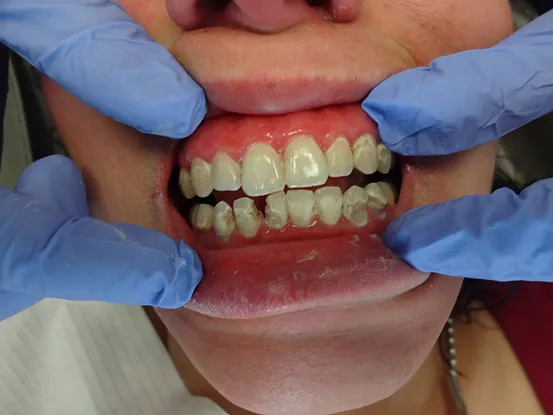

Case 7

38 year old female with extensive cervical caries from a high sugar diet and poor oral hygiene. 12 units of porcelain crowns and composite fillings to restore form and function followed by frequent recall visits